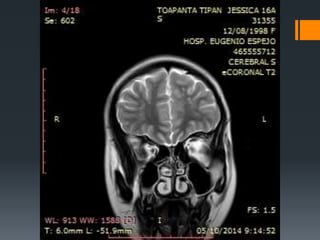

 TC SIMPLE DE CRANEO (30-09-2014)

 RESONANCIA DE CEREBRO (05/10-2014)

TC SIMPLE

Normal

Hipodensidad en ventrículos laterales.

RMN